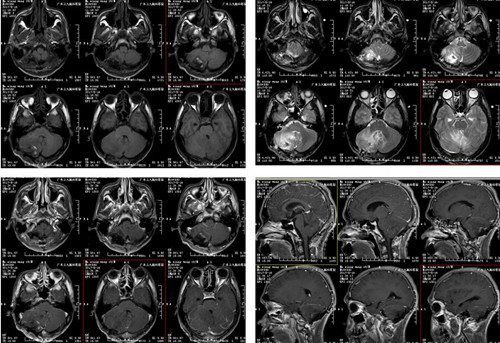

术前头颅MR平扫+增强(轴位+矢状位)

右侧小脑示团块状长T1长T2为主异常信号影、间杂多发斑点状短T1短T2信号影以及流空血管影,FLAIR序列呈高信号为主高低混杂信号影,范围约4.4cm×3.0cm×3.7cm,增强后呈欠均匀明显强化,与邻近脑膜明显紧贴并脑膜增厚强化,邻近脑组织受压、并示大片状长T1长T2水肿信号影。